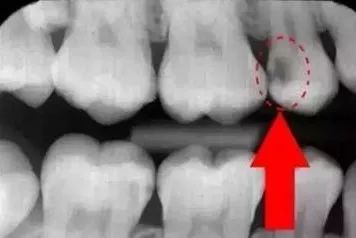

下图圈出来的地方或多或少都有点龋齿,但是有些你并不能看见。这些龋齿还浅不会让你有什么感觉,顶多吃东西塞牙,和冷水敏感而已。

每颗牙都有所龋坏